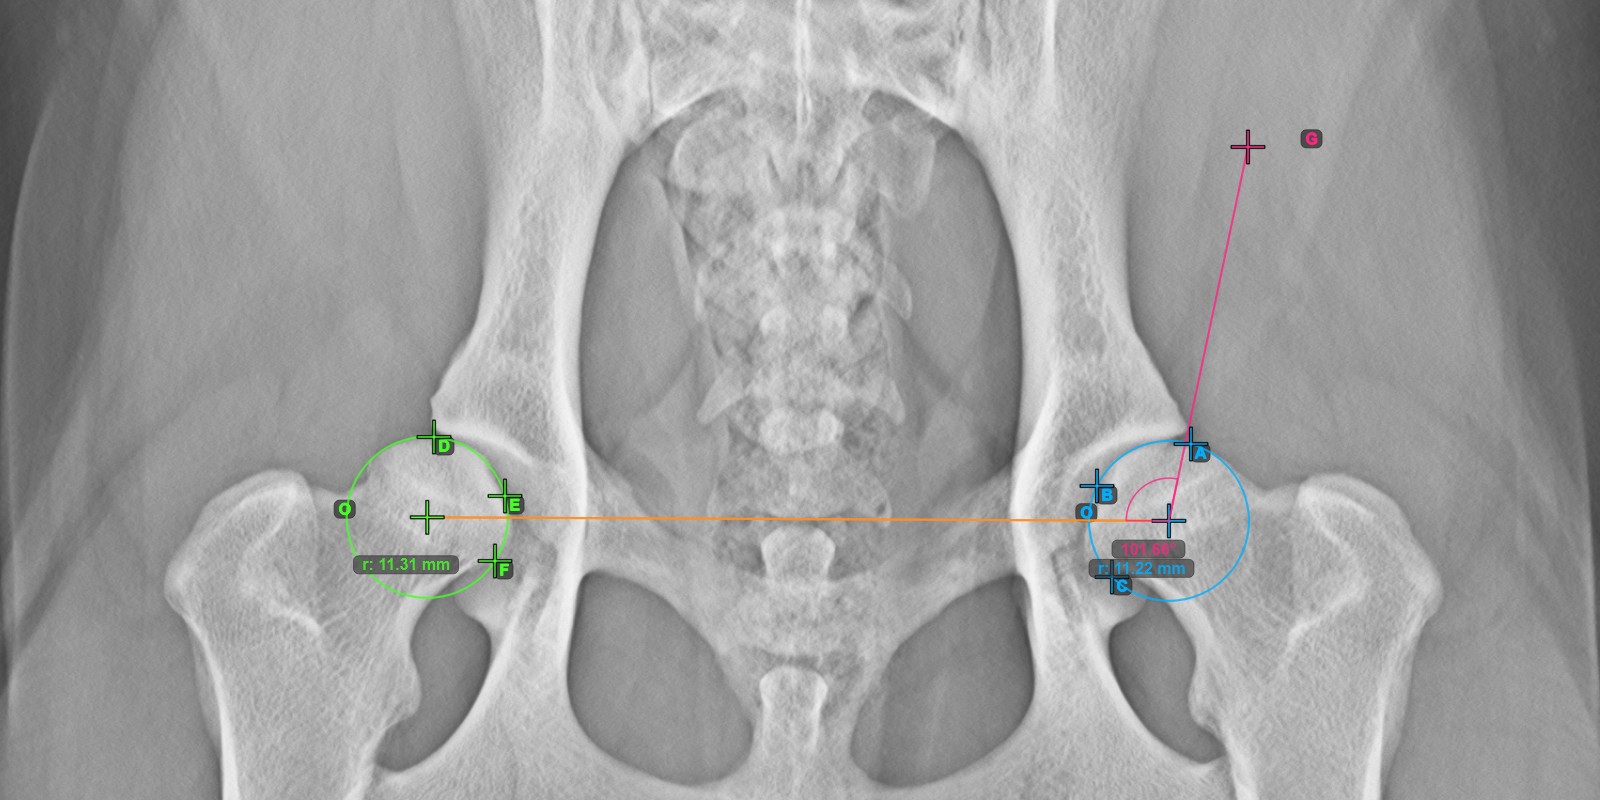

Continue by marking the three points on the articular surface of the right Caput Femoris.

Mark the three points on the articular surface of the right Caput Femoris (outside of the Fovea Capitilis). Regardless of the order, make sure to mark the most cranial point, the most caudal point and the midpoint of the femoral head. A circle will be automatically constructed based on the three placed points.

The origos of the two circles will also automatically be connected by a line, specifying the initial side of the angles yet to be constructed.

The image below depicts the typical placement of the three points on the articular surface of the right Caput Femoris.